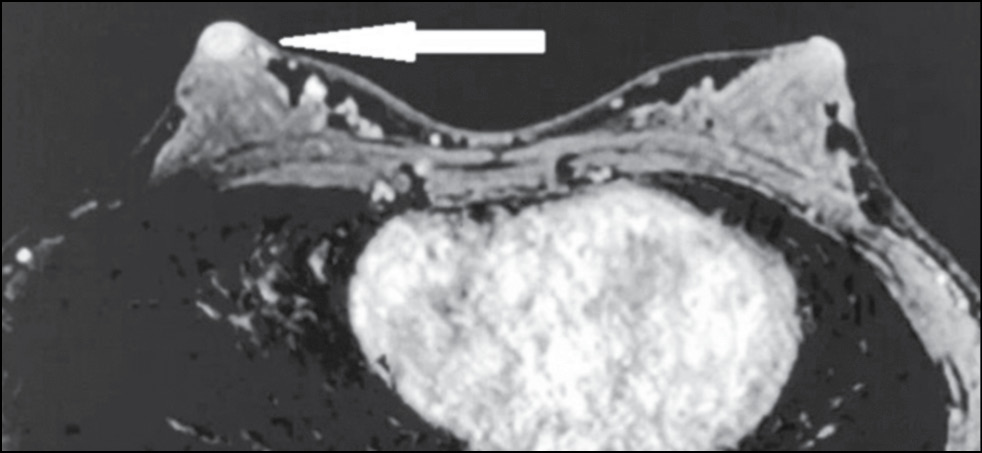

A 59-year-old patient complained of erosive changes in the nipple (Fig. 1). Physical examination revealed erythema, erosion, and nipple retraction. Doppler ultrasonography with color flow mapping revealed increased blood flow in the nipple projection (Fig. 2). Mammography findings were normal. To assess the extent of disease spread, breast MRI with contrast enhancement was performed. The early postcontrast series (Fig. 3) and maximum intensity projection (MIP) images (Fig. 4) showed a segmental contrast retroareolar area from the nipple level to posterior breast sections. Ultrasound-guided core biopsy followed by immunohistochemical analysis revealed Paget’s disease of the nipple with high-grade intraductal carcinoma in situ. Receptors for estrogen (G3 ER) and progesterone (PR) were negative. Oncogenic protein Ki-67 was 45%.

Figure 3. Magnetic resonance imaging of Paget’s disease (early enhancement phase): the retroareolar area of segmental enhancement from the nipple level to the posterior breast (arrow).

Figure 4. Magnetic resonance imaging of Paget’s disease (maximum intensity projection): the retroareolar area of segmental enhancement from the nipple level to the posterior breast (arrow).

In 22%–71% of cases, mammography provides a false-negative result [21], and in this case, breast MRI is indicated to identify abnormalities and deter the extent of disease spread. [20] Characteristic MRI findings include asymmetry, thickening, flattening, retraction of the NAC, and uneven contrast accumulation in this area. MRI allows evaluating adjacent structures and axillary lymph nodes.